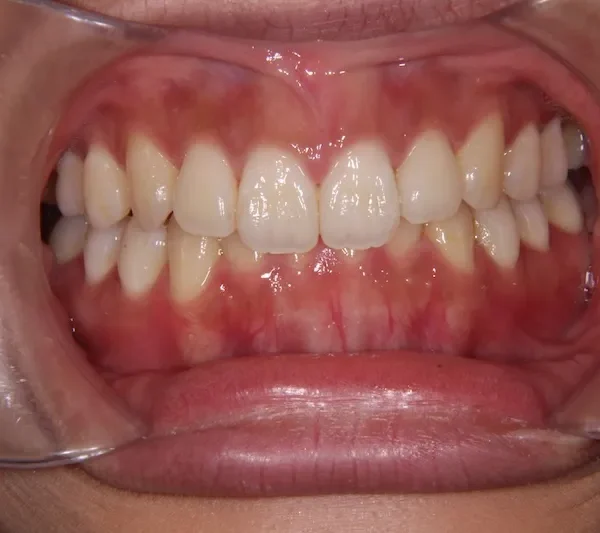

治療経過1

初診時年齢 19~29歳 (女性) 主訴 前歯で物が噛みちぎれない

診断名 開咬・上顎前突 装置名

前歯で物が噛みちぎれないを主訴に来院された患者様です。

非抜歯で、オリジナルリンガルアーチと歯科矯正用アンカースクリューを用いて治療しました。

治療回数15回、1年の治療期間で矯正治療を終了しました。

主訴が改善され、ご満足頂きました。